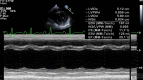

We report a case of thyroid storm precipitated by SARS-CoV-2 infection in an adolescent girl with a history of Graves disease and dilated cardiomyopathy. This case highlights that SARS-CoV-2 infection can potentially trigger a thyrotoxicosis crisis and acute decompensated heart failure in a patient with underlying thyroid disease and myocardial dysfunction even in the absence of multi-system inflammatory syndrome in children. We systematically reviewed the thyrotoxicosis cases with SARS-CoV-2 infection and described its impact on pre-existing dilated cardiomyopathy.